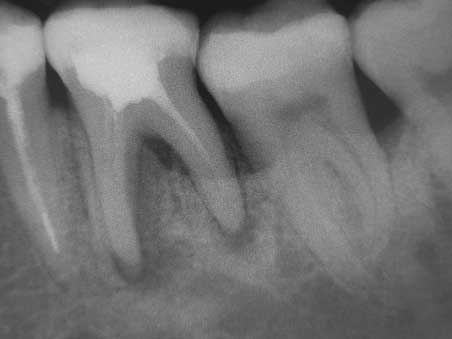

Veröffentlicht 30. November 2008 am 452 × 339 in 3 mesiale Kanalausgänge (1)

Diagnostische Rö -Aufnahme